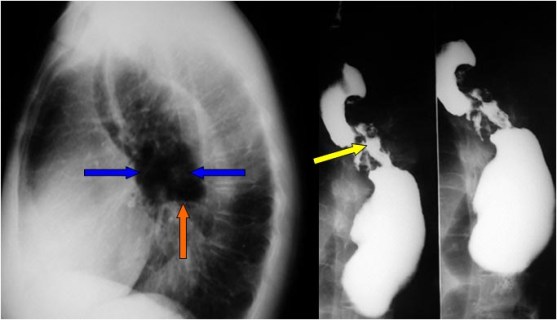

SIGNO DEL PICO

Signo de vólvulo y otras causas de obstrucción intestinal en asa cerrada, que inicialmente se describió en el estudio baritado (enema opaco). Se refiere a la estenosis fusiforme que se dirige al punto de torsión (flecha roja en la radiografía y flecha negra en el esquema). En caso de que el contraste atraviese la estenosis y exista una disminución de la luz en el segmento proximal de la torsión, la imagen obtenida recuerda a la de dos pájaros con sus picos juntos.

La imagen muestran el Signo del pico en un paciente con un vólvulo de sigma.

Aunque lo hemos incluido dentro de los signos de colon, este signo también es visible en las obstrucciones en asa cerrada de intestino delgado.

Inicialmente descrito en el enema opaco, en la TC también es visible este signo y no solamente en el asa eferente (como ocurre en el enema opaco, donde este asa se rellena retrógradamente) sino también en el aferente.

Existe otro Signo del pico en la achalasia, afectando al esófago distal, ya descrito en la sección correspondiente (ABDOMEN/Tubo digestivo/Esófago).